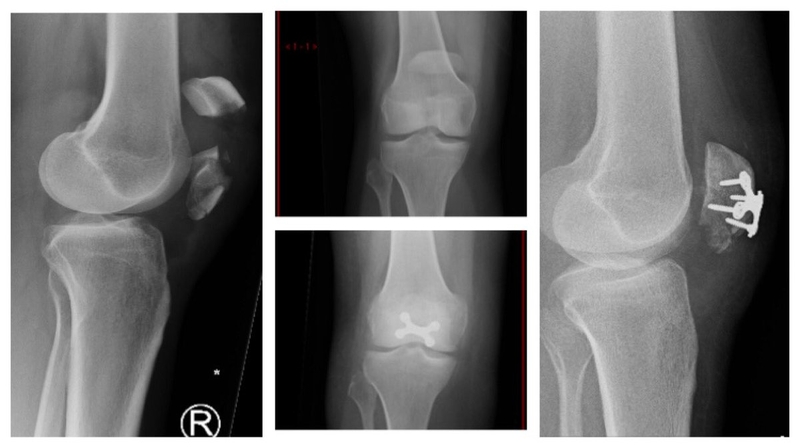

Người bệnh đến với bác sĩ sẽ được thăm hỏi về tiền sử chấn thương, sau đó là thăm khám đầu gối và chụp X - quang. Bằng phương pháp nhìn và sờ bác sĩ sẽ xác định được mảnh xương bánh chè có bị di lệch hay không, có hiện tượng tụ máu hay không.

Chụp X - quang hai bên khớp gối là bắt buộc bởi chúng sẽ cho thấy tổn thương của xương bánh chè cũng như các cấu trúc xương xung quanh. Trong các trường hợp nghi ngờ gãy xương liên tục hoặc có chấn thương dây chằng, sụn chêm, sụn đầu gối kèm theo.

Chụp X - quang xương bánh chè